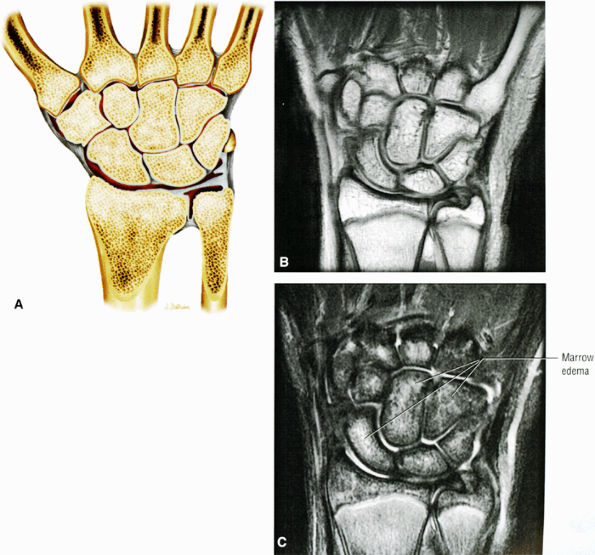

![]() |

FIGURE 10.56 ● (A) An anterior view of the distal ends of the radius and ulna. The bones have been separated to reveal the ulnar notch. (B) Corresponding scaphoid and lunate fossa on coronal PD FSE image. The scaphoid has five articulations: the trapezium and trapezoid distally, the radius proximally, and the capitate and lunate medially. The lunate articulates with five bones: the radius proximally, the capitate and hamate distally, the scaphoid laterally, and the triquetrum medially.